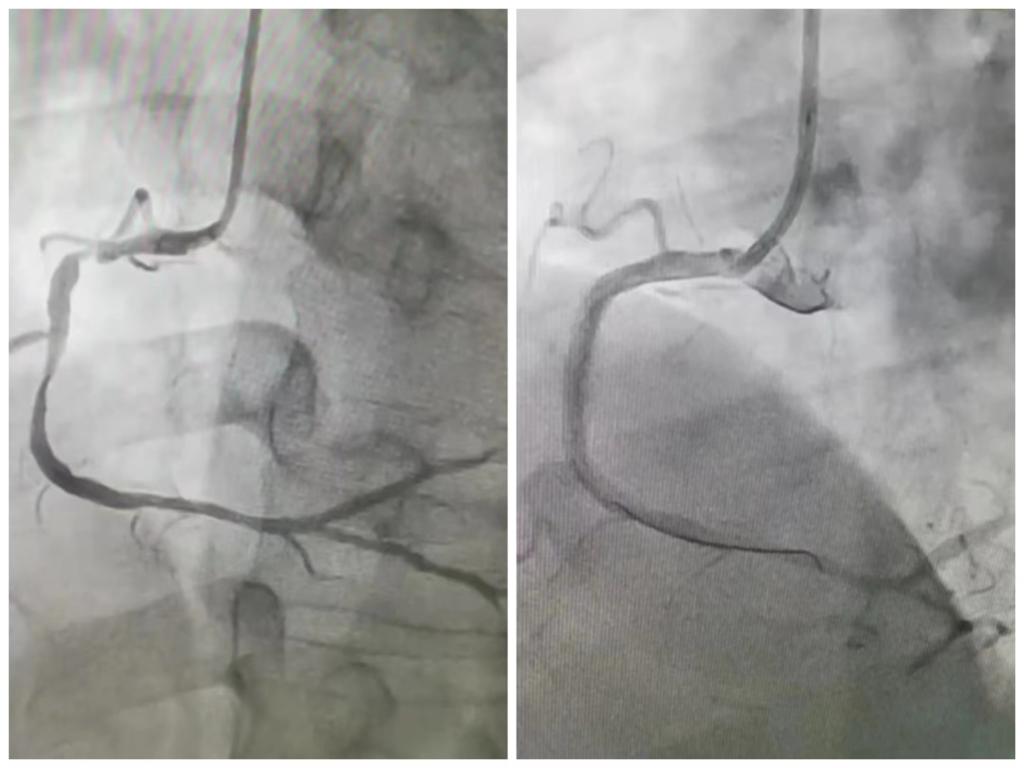

随即快速启动院内绿色通道,胸痛中心团队迅速就位,在取得患方签字同意后立即为患者急诊行冠状动脉造影检查,结果显示患者粗大的右冠状动脉近中段多处严重狭窄,局部血栓影,随时有再次闭塞导致心源性猝死风险。

胸痛中心团队密切配合,迅速将导丝通过罪犯血管,给予球囊扩张后于右冠状动脉病变部位植入支架,复查造影提示右冠状动脉血流通畅,成功解除”罪犯“血管病变,术后复查心电图下壁导联ST段回落至基线。